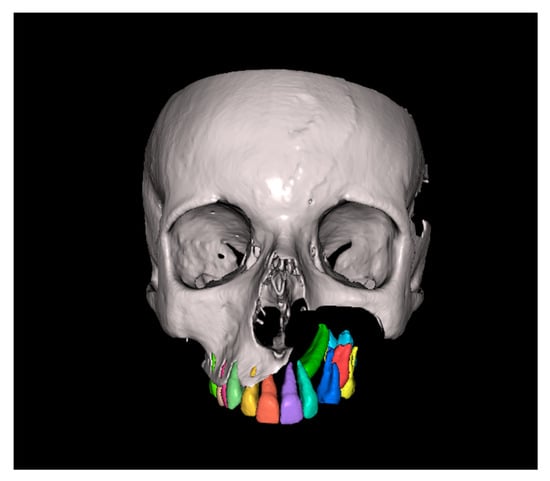

Since the IC is not visible in the initial STL, it was necessary to know its three-dimensional location. As performed in the other method, the initial CBCT scan (Figure 2) was opened in the program, and all teeth were segmented. Although Figure 2 shows the skull model, only the teeth segmentation is necessary for this method. A small cut was made to allow visualization of the IC (Figure 3).

Figure 2.

Initial CBCT scan.

Figure 3.

Initial CBCT after tooth segmentation.

A 13-year-old male patient presented with Class II Division 2 malocclusion, a bilateral Class II sagittal relationship, and retroclined incisors. Cone-beam computed tomography revealed a palatally impacted maxillary left canine (tooth 23), with its cusp located palatally to the apical half of the left lateral incisor. The root exhibited significant apical curvature, extending toward the floor of the maxillary sinus (Figure 12 and Figure 13), making spontaneous eruption unlikely.

Figure 12.

Figure 13.

Impacted canine 23 with its cusp palatally positioned to the apical half of the left lateral incisor, with the root significantly curved and inserted into the maxillary sinus.